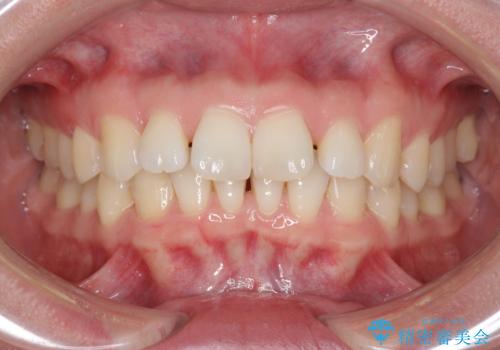

- 前歯の突出感、出っ歯の治療を希望され来院されました。

インビザラインを用いた治療計画を立て、しっかりと出っ歯を治すためにマイクロインプラントを併用します。

マイクロインプラントを併用することでしっかりとマウスピース全体を後方へ引き、前歯の突出感を改善することができました。